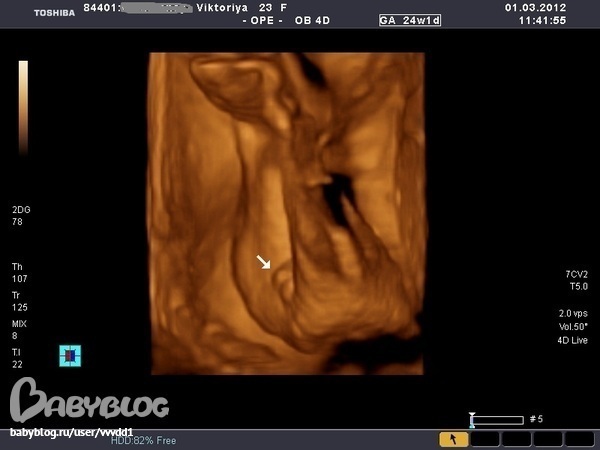

Вопросы про УЗИ, обследования и анализы: что, где, как, когда?Девченки,кто разбирается,посмотрите на фотку,как вы думаете это девочка или мальчик?Мне 2 врача сказали девочка,а родственники мои задурили мне голову,все хорохом говорят,что это похоже на достоинство мальчика,муж тоже так считает,я начинаю теперь сомневаться.Если есть возможность,покажите фотку мальчика.

не видно извините пиписьки) у меня у малыша на экране было между мошонок пиписька) ну а вообще фото класс мой не давал себя так сфотать)блин спорно я думаю что девочка может органы половые ещё недастаточно сформировались. Да я за девочку)) хотя бы сужу по фото своего малышастика

Викусь, это девчушечка! По второй фотке видно, что нет писюна

Мне кажется, что мальчик. Но Узист знает лучше, ведь половые органы мальчика и девочки расположены под разным углом.